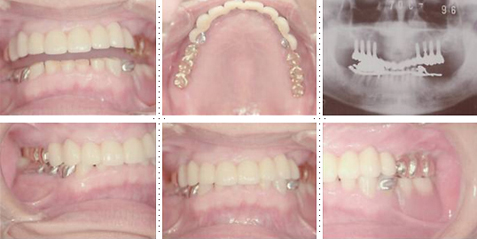

症例1

58才 女性

嘔吐反応が激しく入れ歯を入れると気持ち悪くなってしまうと、インプラント希望で来院されました。

上顎左右奥に4本ずつ計8本のインプラント埋入。下顎左右奥に3本ずつ計6本のインプラント埋入上下顎とも全体的にセラミックを使用した冠をセット。